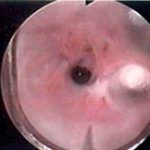

- Uretrotomia interna: um tipo especial de material denominado uretrótomo é introduzido pela uretra até o local da estenose. Uma pequena lâmina embutida corta o tecido fibrótico em toda a sua extensão, reestabelecendo a luz da uretra. Cerca de 30% dos pacientes apresenta cura. Alguns devem ser novamente submetidos ao procedimento pela recorrência na formação do tecido cicatricial. Trata-se de um método atraente por ser realizado de maneira endoscópica, minimamente invasiva, sendo mais indicado para estenoses curtas (< 1.5 cm).

Imagens endoscópicas de procedimento de uretrotomia interna, desde a estenose até a sua resolução